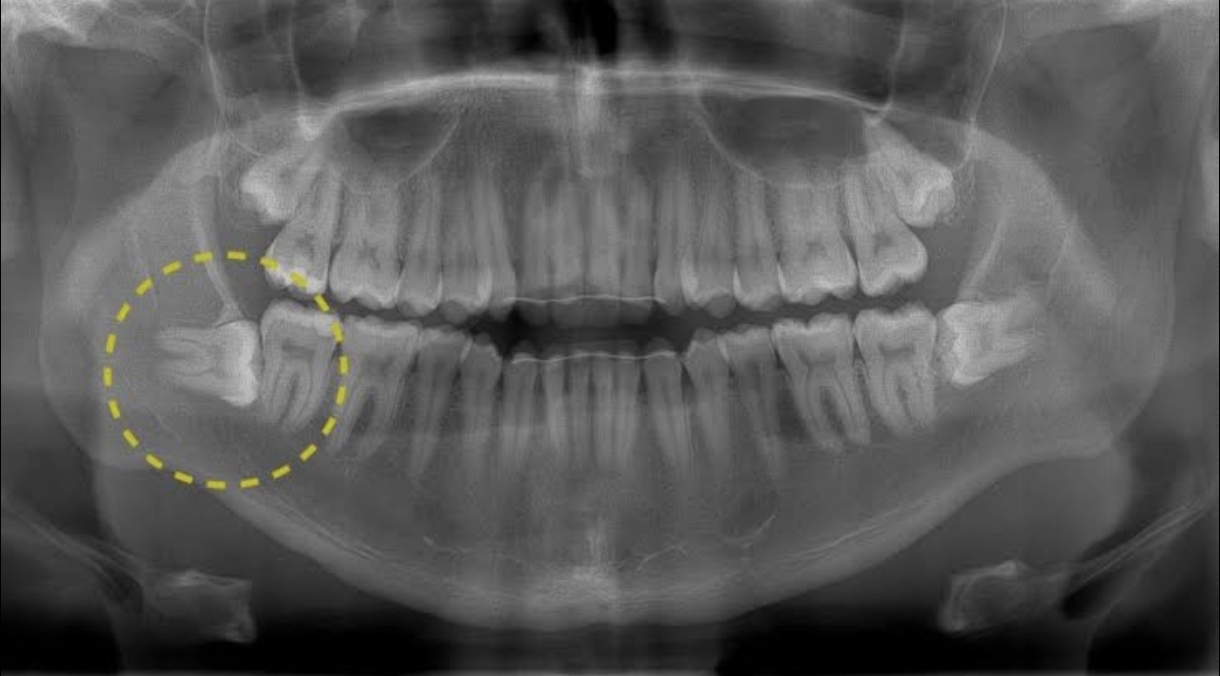

Прореразались у меня зубы мудрости. Да так удачно, что и не почувствовала. Да так не удачно, что нижние с дистопией. Узнала я об этом на ежегодном ТО полости рта. Приговор обжалованию не подлежит - удалить, нельзя оставить.

Хожу я по ОМС и стоматолог-терапевт направил к хирургу-стоматологу, который сразу развернул в областную, потому что только там берут такую красоту. Направление то есть, но нужно же талончик получить. Звоним, звоним, ещё звоним... Ура, ближайшая запись через 13 дней. Ну мне не экстренно, можно и подождать.

Удаление левой восьмёрки я избегала всеми силами, не болит и ладно. Но вот опять звучит приговор "А чего тянем, тут уже кариес, пульпит захотела. Нет, мы такие не удаляем, иди в областную". Дорожка протоптана, талончик на руках, ждём-с.